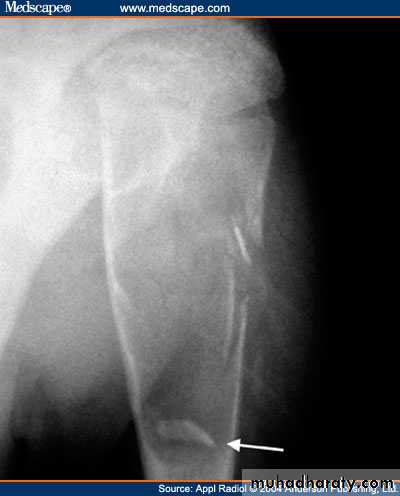

X-ray shows translucent cystic lesion in the metaphysis and shaft of bone with bone widening and cortical expansion and thinning with possible pathological fracture.It may show bridges of calcification inside as a result of healing of micro fractures that commonly occurs,

by this way it may gradually disappear and heals later in life;

sometimes we use this criteria as a method of treatment by frequent aspiration and local steroid injections aiming at induction of such micro fractures that aids healing